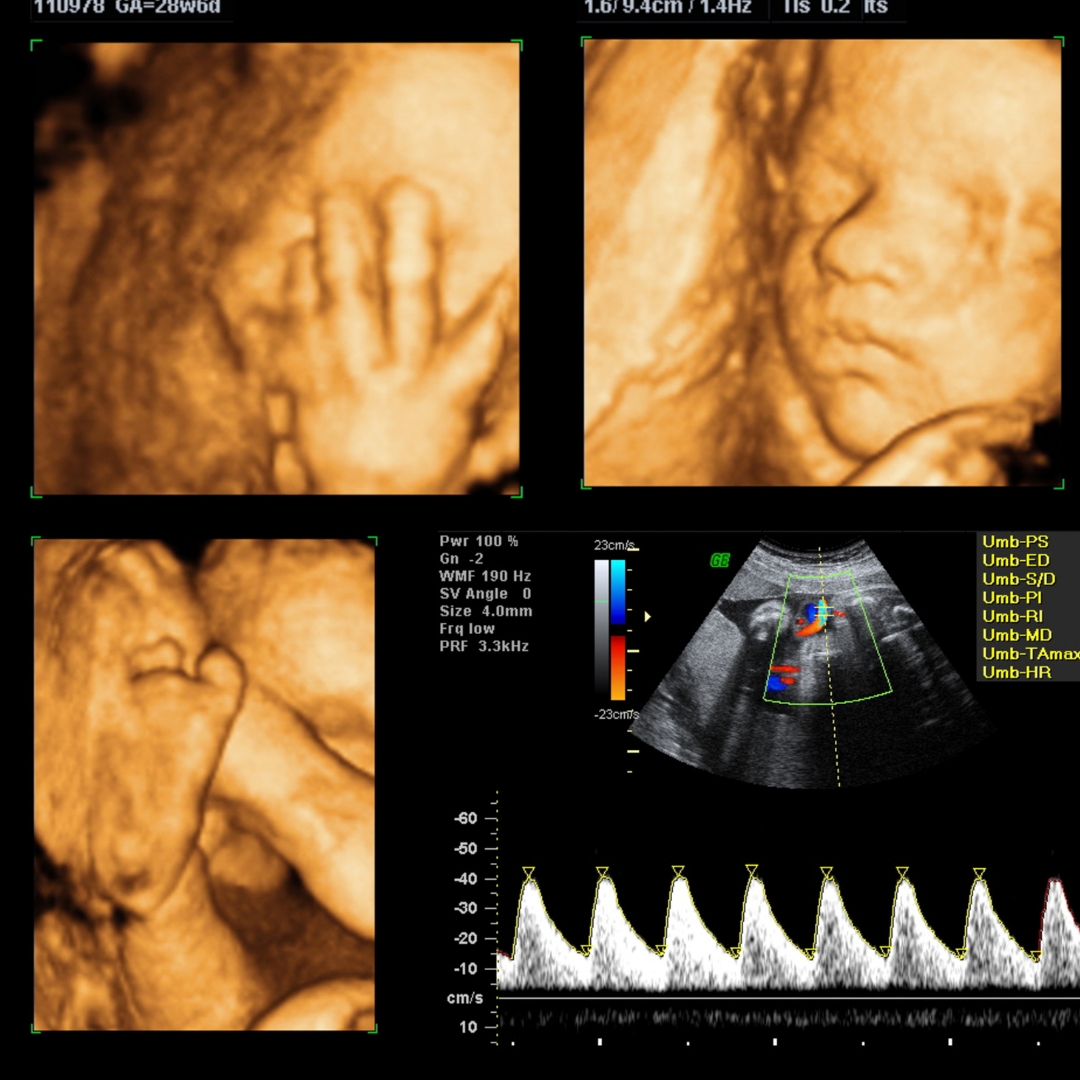

Fetal Anomaly Scan

We came in worried during our second trimester, but the clarity and care we received here was unmatched. The fetal scan was detailed, and the doctor explained every step patiently.

Fetal Growth Scan

From ECG to fetal Doppler and counseling — everything was smooth, clear, and timely. The staff is kind, the place is hygienic, and the doctors are genuinely caring.

Fetal Echocardiography

We got a fetal echocardiography done here and were amazed by the precision and care. The radiologist even coordinated with our pediatric cardiologist. That’s rare and valuable.